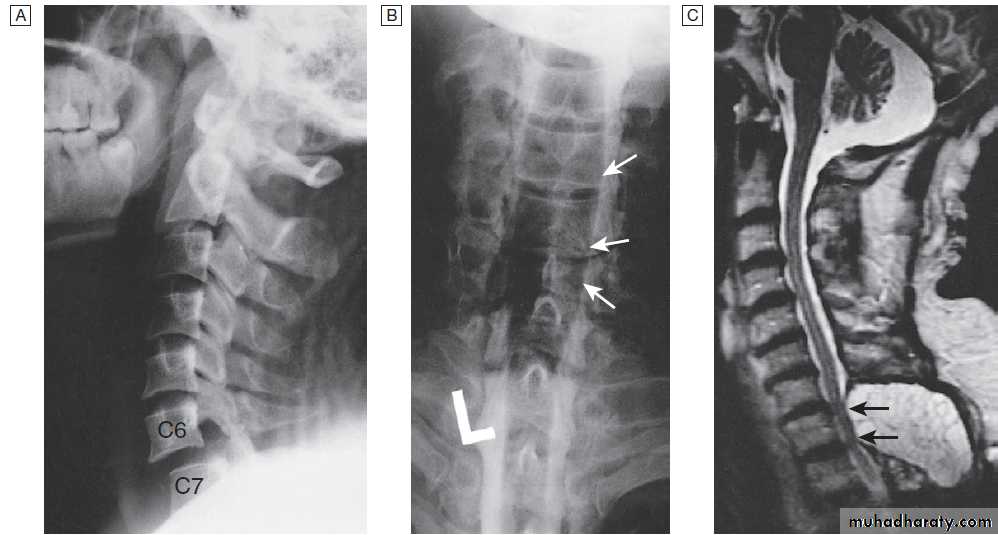

Cervical, thoracic and lumbar spine

Plain X-rays are useful in the investigation of trauma toVertebrae. MRI has transformed the investigation of these areas, since it can give information not only about the vertebrae and intervertebral discs, but also about their effects on the spinal cord and nerve roots.

Myelography is an invasive technique involving injection of contrast into the lumbar theca. While the outline of the nerve roots and spinal cord provides information about abnormal structure, the accuracy and wide availability of MRI have reduced the need for this.

Myelography may still be used for technical reasons or where MRI is unavailable, contraindicated, or precluded by the patient’s claustrophobia.

Different techniques of imaging the cervical spine. A Lateral X-ray showing bilateral C6/7 facet dislocation. B Myelogram showing

widening of cervical cord due to astrocytoma (arrows). C MRI showing posterior epidural compression from adenocarcinomatous metastasis to the posterior arch of T1 (arrows).